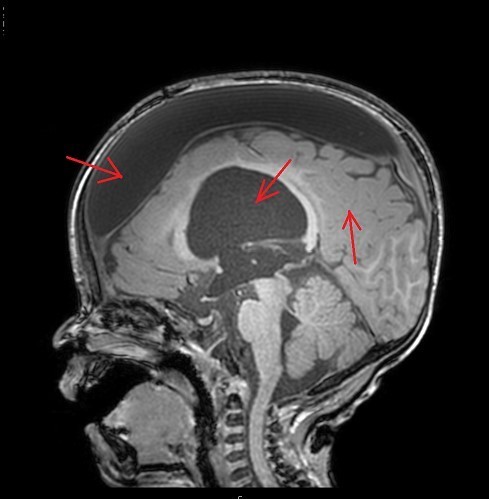

1) CT, MRI 촬영 : 지주막낭종의 크기, 모양, 위치를 확인합니다.